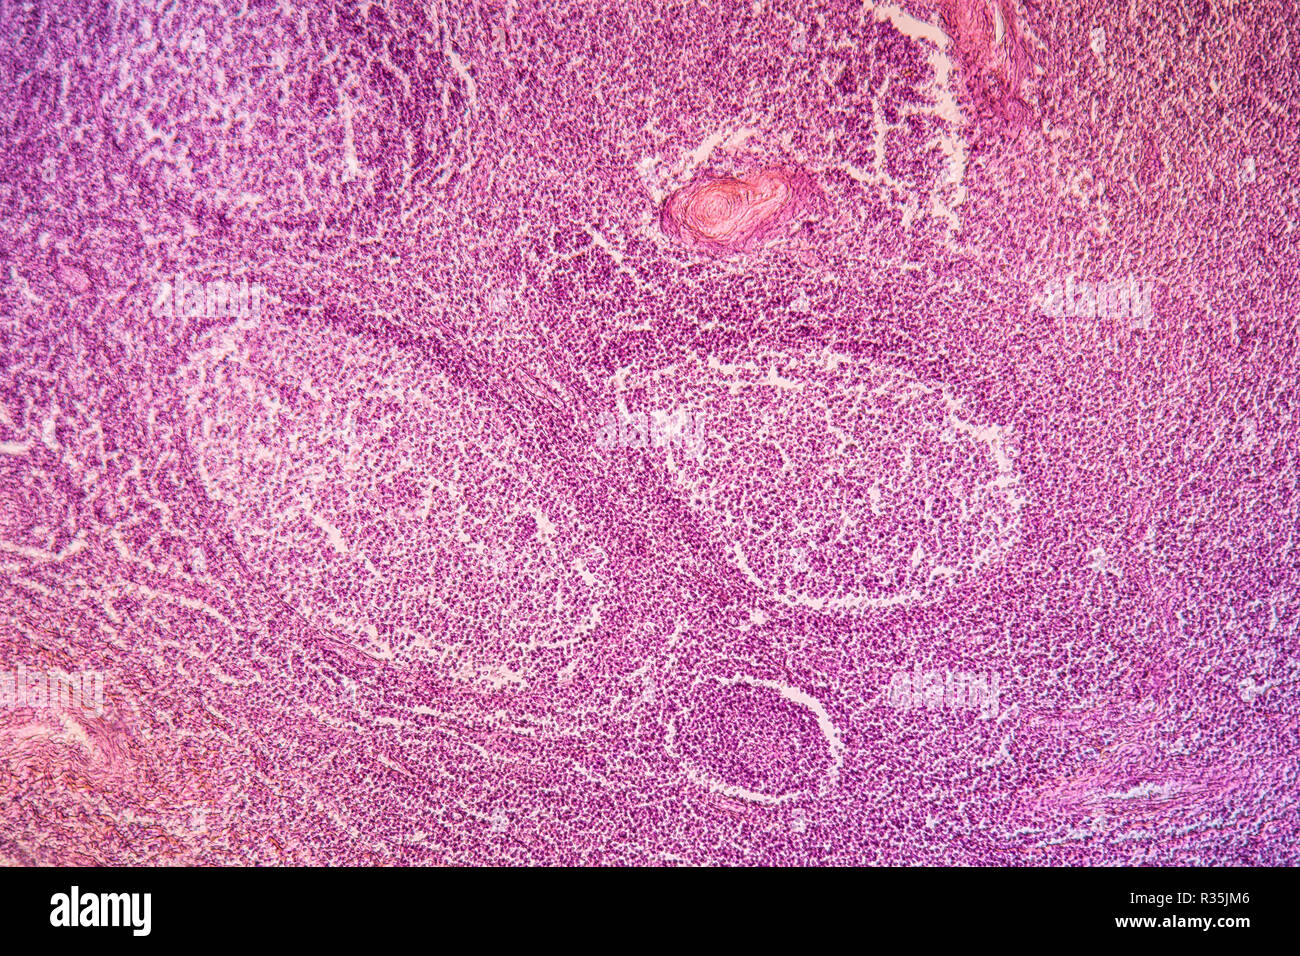

Mandelentzündung Stockfotohttps://www.alamy.de/image-license-details/?v=1https://www.alamy.de/mandelentzundung-image225703190.html

Mandelentzündung Stockfotohttps://www.alamy.de/image-license-details/?v=1https://www.alamy.de/mandelentzundung-image225703190.htmlRFR35JM6–Mandelentzündung